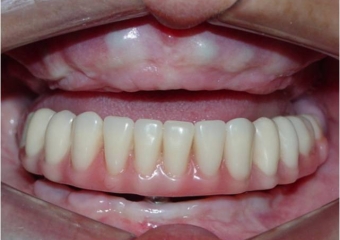

Sorriso final do caso terminado em outubro de 2012 - Clínica Cliniface

Sorriso final do caso terminado em outubro de 2012